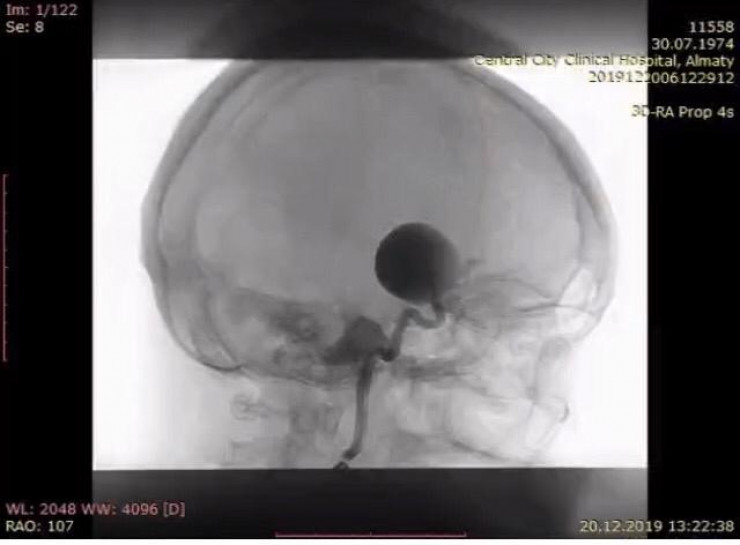

- Откровенно говоря, нам есть что предложить. Одним из важных событий 2019 года было открытие единственной на территории СНГ операционной ангиографической системы Philips Azurion 7. Система поддерживает визуализацию всего тела и обеспечивает доступ к пациенту со всех сторон, поэтому исследование сосудов становится более эффективным, благодаря получению анатомических изображений видны даже элементы мелких сосудов. Теперь всем, кому необходимо провести исследование или операцию при выявленных поражениях и пороках развития кровеносных сосудов, можно обратиться к нам, где все подробно расскажут, объяснят и при необходимости прооперируют.

Фото Совминки. Гигантская аневризма